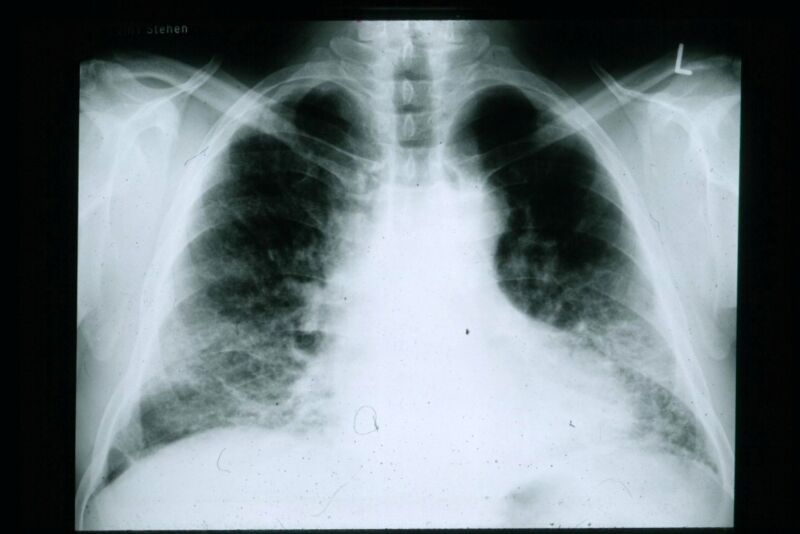

No where to collapse the lung

No where to collapse the lung

No where to collapse the lung

No where to collapse the lung